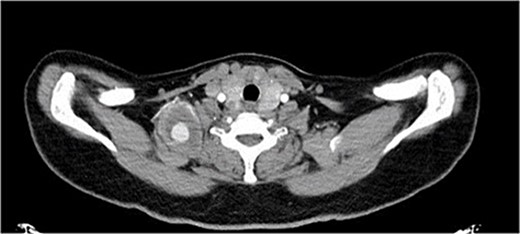

A 40-year-old female, who is a known case of type 1 diabetes mellitus, and hypothyroidism, on insulin and levothyroxine, was referred to our institute 4 months ago following trauma to her right shoulder from a falling drawer: complaining of swelling and pain around the right shoulder, palpable right distal pulses, and no discoloration or skin changes. Computed tomography angiography (CTA) showed partially thrombosed pseudoaneurysm at the right subclavian artery measuring 4.5 × 4 × 3.1 cm, most likely at the level of the costocervical trunk, specifically the highest intercostal artery (Figs 1 and 2). The subclavian artery and its branches were patent.

The patient underwent open repair of the pseudoaneurysm. Procedure details: a 2 cm supraclavicular transverse incision was made, the subplatysmal flap was raised and the underlying fat pad was dissected, exposing the scalenus anterior muscle. Pseudoaneurysm was found on the transverse cervical branch of the subclavian, imbedded within the scalenus medius muscle. C-5, C-6, and the long thoracic nerves were identified (Fig. 2). Pseudoaneurysm was mobilized, inflow was controlled by 2–0 silk stitch and clips. The pseudoaneurysm was resected completely (Figs 3 and 4). The patient tolerated the procedure and was discharged without reported complications.